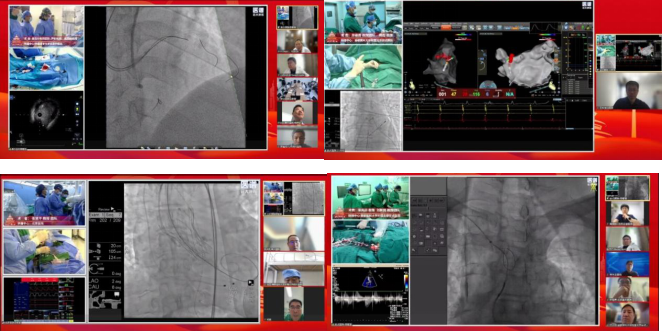

6月20日上午,中国医学科学院阜外医院、北京医院、首都医科大学附属北京安贞医院的顶级专家团队进行线上手术演示,为心血管医生带来了一场视觉与技术的双重盛宴,这也是本次会议突出的亮点之一。本次手术转播共涵盖冠脉、电生理、结构性心脏病3大版块,完成12台高难度手术,共吸引了全国34个省、市、自治区的心血管医护同仁共同关注,线上观看点击量高达78 928人次。

线上手术演示专场

专家们在手术过程中的实时讲解、点评,让线上观看的医生能够深入理解手术原理与操作要点,防止并发症的发生,这对提升基层医生的诊疗水平、推动心血管疾病治疗技术的普及与发展意义重大,同时也启发广大医生在临床实践中不断探索创新,追求技术的精益求精,从而为患者带来更优质、更高效的医疗服务。